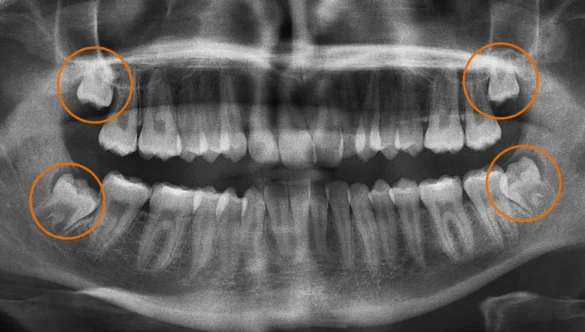

At Nova Dental Hospital, our CBCT technology supports:

- Implant planning

- Root canal assessment

- Bone analysis

- Wisdom tooth diagnosis

- Jaw evaluation

- Complex restorative planning

This allows us to provide more informed treatment recommendations and better long-term support.